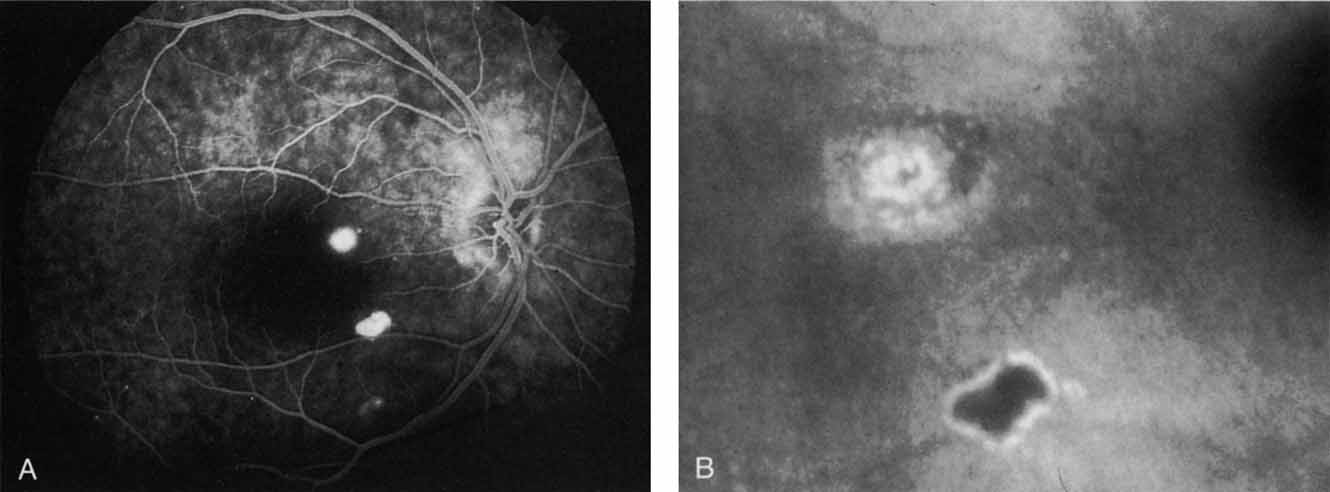

Unlike fluorescein angiography, however, ICG angiographic studies have pointed out that certain principles of laser photocoagulation treatment may not hold with this new imaging capability. This is particularly true with the concept that all areas of CNV need to be obliterated to achieve a successful anatomic result. A careful evaluation of ICG angiograms in some patients with occult CNV has revealed that two forms of neovascular lesions may exist: (1) localized, intensely hyperfluorescent leaking areas of “active” CNV; and (2) more subtle and larger areas of hyperfluorescence with minimal leakage, representing “quiescent” portions of the neovascular complex (Fig. 8). A pilot study by Guyer and colleagues22 demonstrated that localized photocoagulation treatment applied to the active area of CNV alone might result in successful and long-term anatomic stabilization and improvement in the visual acuity in some patients (Fig. 9). A subsequent review of these lesions has demonstrated that they may represent a subpopulation of occult CNV known as polypoidal choroidal neovascularization, described later.